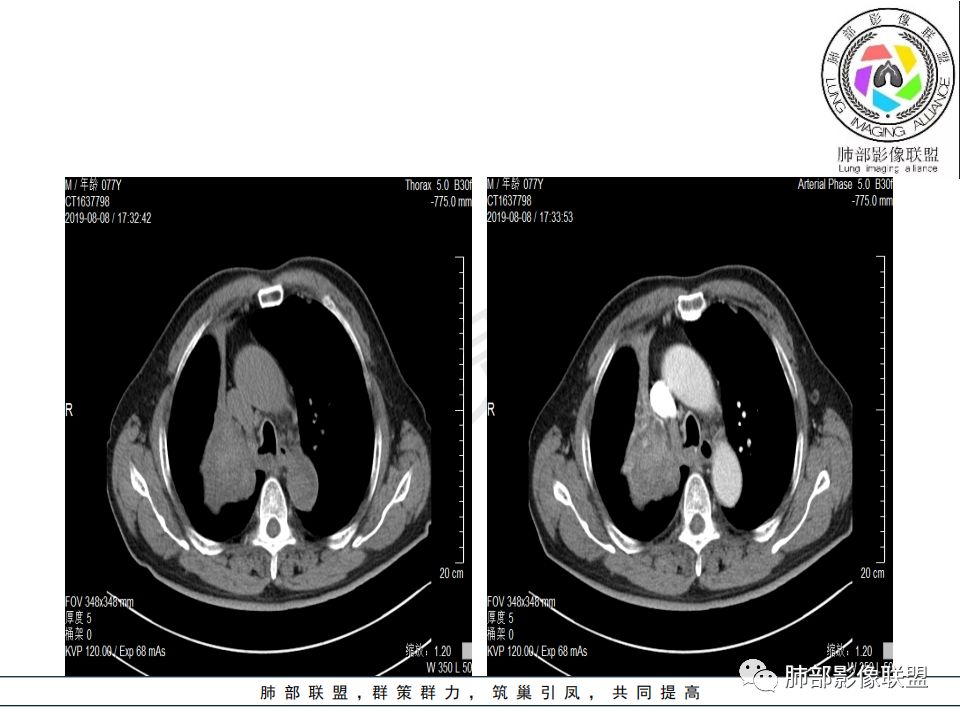

病史:男.77岁,咳嗽1月;干咳,少许白痰,无发热,2013胃癌术后,角蛋白24.65(0-3.07),SCC和proGRP不高;

影像:影像右侧大支气管阻塞,临床没有症状或很轻微,要想到胃腺癌转移;胸壁代偿好,透亮度稍低不明显,慢性过程;34.8-52.5HU,主病灶支气管前壁另有1结节,都做成增强两期了,动脉期较平扫有强化;

晨读:患者老年男性,以咳嗽一月就诊,少量白痰,胸CT:纵隔右移,右肺体积缩小,气管下段管壁可见结节样改变,气管软骨变形,气管下段及右主支气管可见新生物向管壁浸润,并向管腔外生长,右上肺肺不张,但不张边缘可见病灶呈膨胀性生长,可见分叶,增强后强化明显。考虑:肺部恶性病变(鳞癌?)

右肺上叶肿块,边缘光滑,略膨隆,近段支气管堵塞,平扫密度均匀,增强后不均匀强化,其内可见不规则血管和坏死,纵隔淋巴结肿大,老年男性,无感染性病史,综合考虑恶性肿瘤(鳞癌,腺癌),鉴别:OP(一般下叶多见)

从强化情况和冠状位看主要还是从外向内的一个肿块,有不张,但不张范围不大,近端支气管堵塞,考虑腺癌或类癌(原发或转移都可能),鉴别鳞癌。